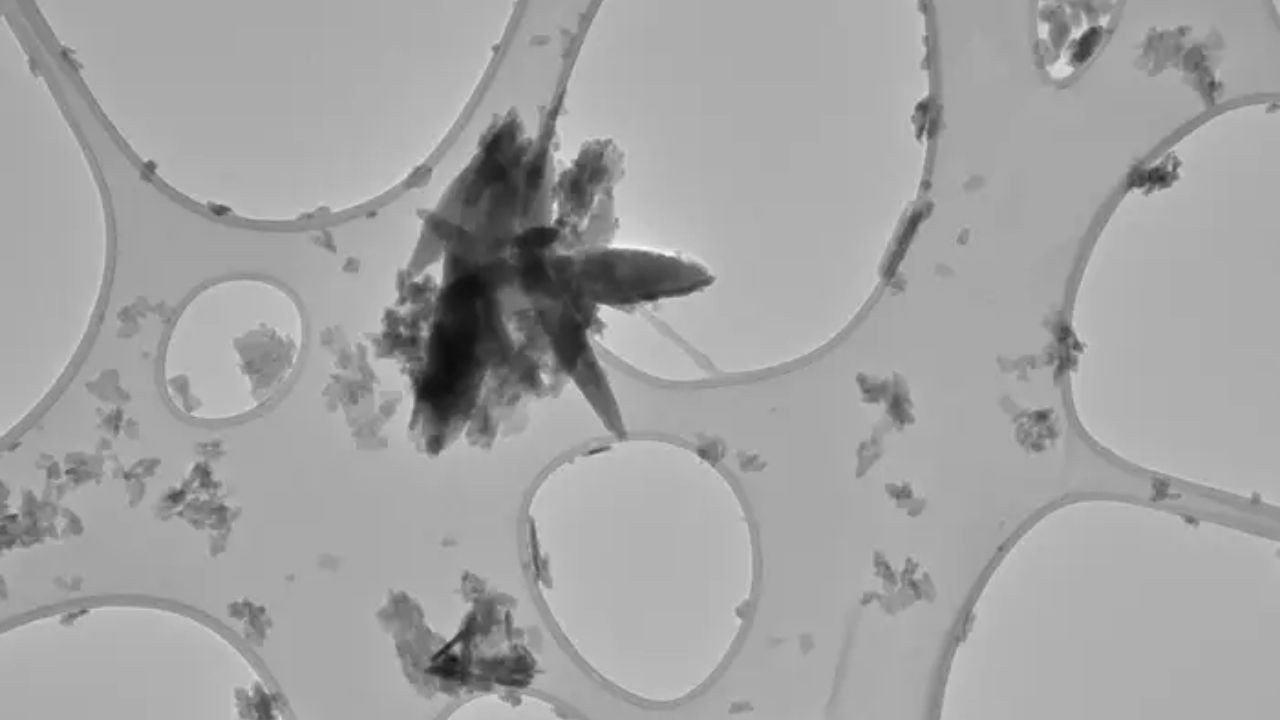

Bilim insanı ekibiyle birlikte atardamarlarda birikebilen ve bunun sonucunda kan akışını engelleyerek felce ya da kalp krizine neden olan yağlı plakları inceledi.

Sağlıklı, plak içermeyen atardamarların duvarlarıyla karşılaştırıldığında semptom göstermeyen kişilerdeki plaklarda 16 kat daha fazla plastik olduğu görüldü. Felç ya da görme kaybı yaşayan kişilerdeki plaklardaysa 51 kat daha fazla plastik tespit edilmişti.

Clark 48 kişinin atardamarından alınan örnekleri incelediğinde plaklardaki mikroplastik miktarının değişken olduğunu fark etti. Daha da endişe verici olanı, plaklardaki hücrelerin hangi genleri aktive edip devre dışı bıraktığıydı.